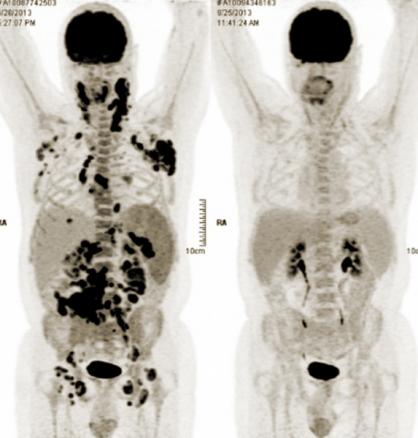

lymphome B diffus à grandes cellules avec atteinte sus- et sous-diaphragmatique

TEP-TDM : bilan initial (à gauche) et réévaluation en fin de traitement (à droite).